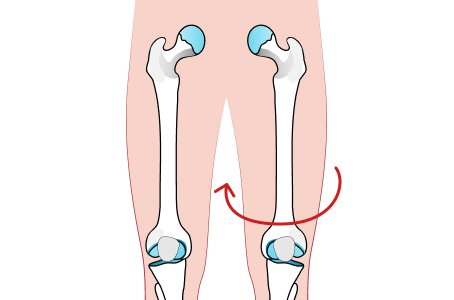

대퇴골 내회전

허벅지 뼈가 안쪽으로 틀어진 경우

경골 내회전

종아리 뼈가 안쪽으로 틀어진 경우

2. 걷거나 서 있을 때 무릎이 정면을 보고 있지 않고 약간 안쪽을 보고 있거나, 천장을 보고 누워 있을 때에 양쪽 발끝이 안쪽으로 모여 있다면 안짱다리를 의심해 볼 수 있습니다.

3. 양쪽 발을 붙이고 섰을 때 무릎 사이에 주먹이 들어간다면 안짱다리를 의심해 볼 수 있습니다.